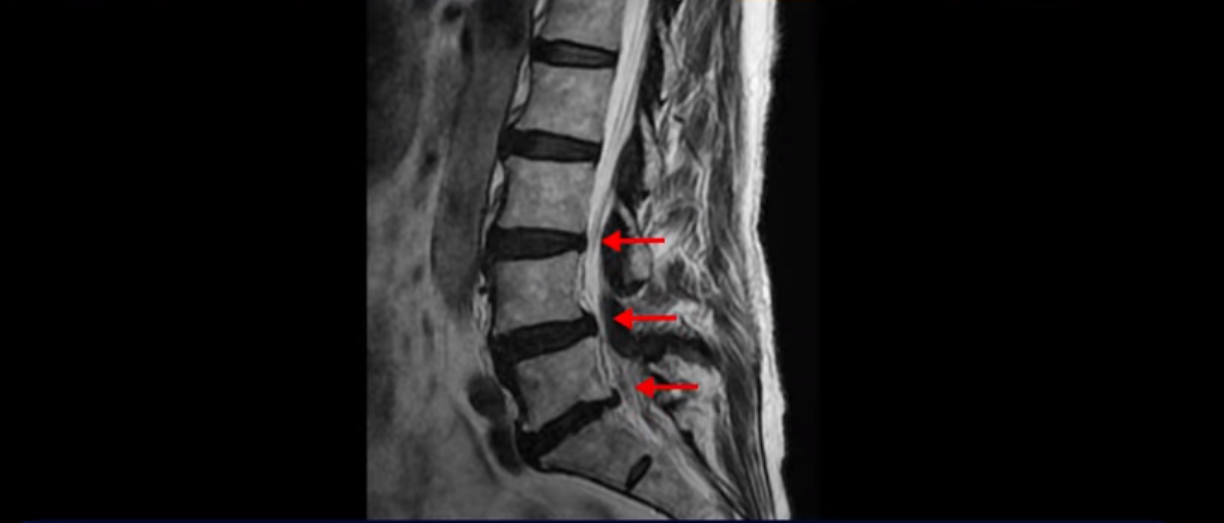

MRI를 보면 척추 여러 마디가 퇴행되어 있고

척추관도 좁아져 있고

특히 왼쪽 신경가지가 빠져나가는 4번 5번, 5번 1번 추간공들이 많이 좁아져 있습니다.